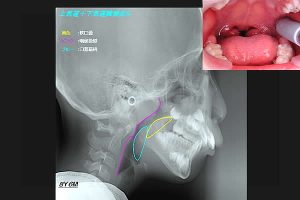

(図2)

扁桃腺の腫れ

これも外気のせいである。そこで、幼稚園や小学校で口唇閉鎖力を測ってみた。

さて扁桃腺が腫れている子ども達の、X線側貌セファロ写真を撮影してみた。まず、鼻呼吸をしている男児。

(図4)

扁桃腺が腫れている子ども達のX線側貌セファロ写真

ピンクは咽頭後壁。黄色は軟口蓋である。軟口蓋と咽頭後壁の間にが、気道が見える。これが正常像。次に、鼻閉のため口呼吸をしている男児。